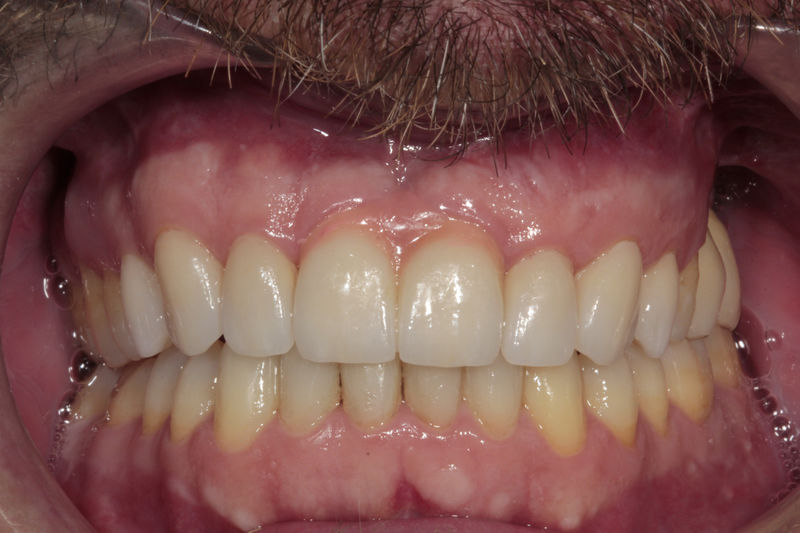

Implante fracasado, extracción, carillas, coronas y prótesis fija.

Implantes, ortodoncia y coronas.

Ortodoncia y coronas.

Cirugía ortognática, implantes, carillas y coronas,